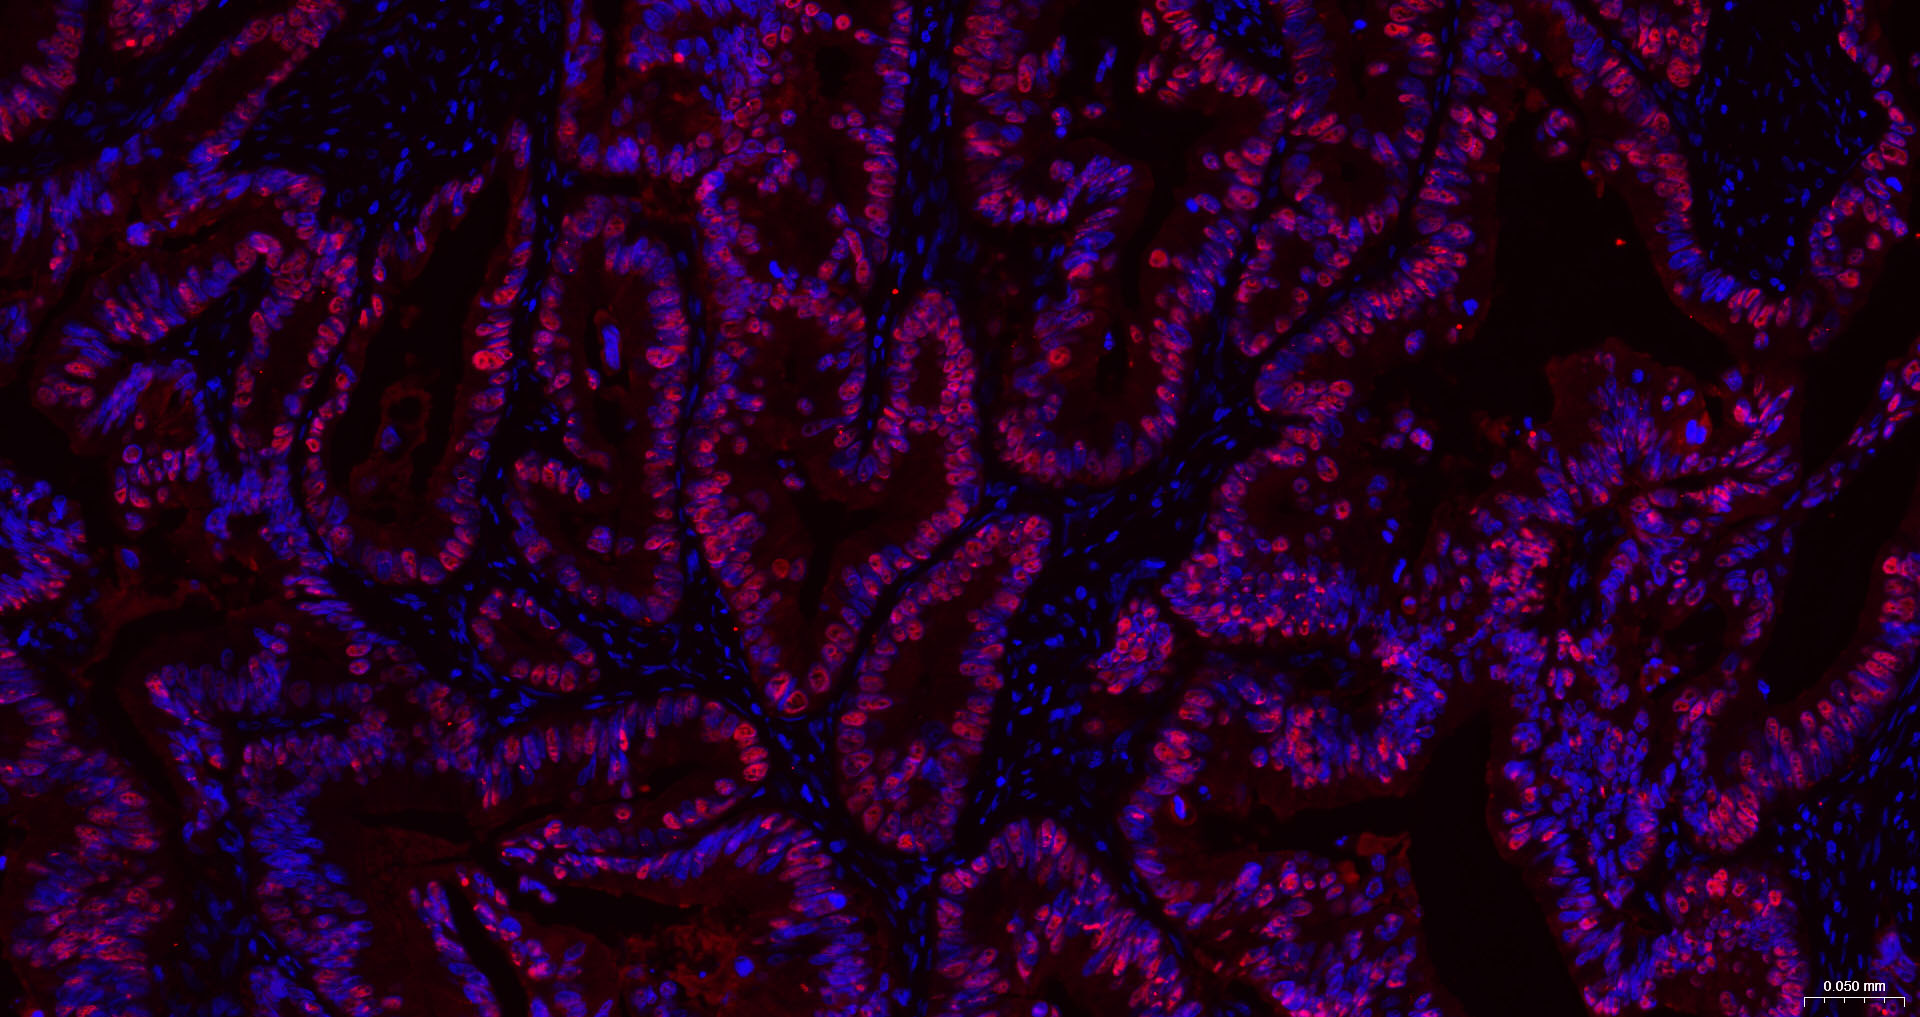

• IHC-P

IHC-P IHC-P1:200-1000